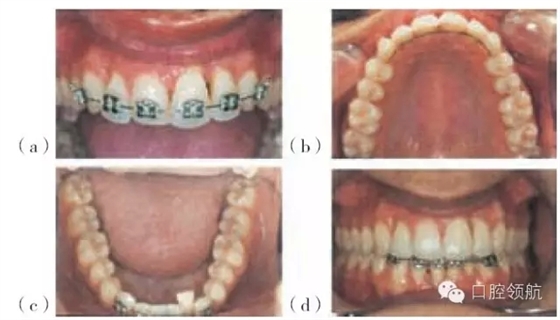

圖29.7 (a,b)圖29.4患者牙周治療之后的圖片,該患者不喜歡左下中切牙的位置及外觀,并希望盡可能保留該牙齒(有唇塌陷和局限性退縮)

圖29.8 圖29.7患者正畸治療的過程:(a)上頜固定矯治器。(b)上頜腭側(cè)保持器。(c)下頜固定矯治器。(d)排齊(永久保持)的上頜前牙及下頜固定矯治器。

左上中切牙經(jīng)正畸治療后更加美觀